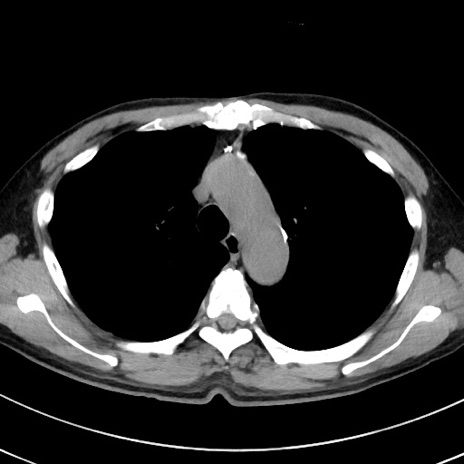

症例38(横断像)

【症例】70歳代 男性

【主訴】腹痛・嘔吐

【現病歴】昨晩より、嘔吐・腹痛あり。今朝になっても嘔吐あり。来院。

【既往歴】心臓バイパス手術、開腹胆摘、腸閉塞

【身体所見】BP 107/71mmHg、HR 116/min、腹部:平坦、軟、下腹部に軽度圧痛あり。反跳痛なし。

【データ】WBC 15100、CRP 0.32